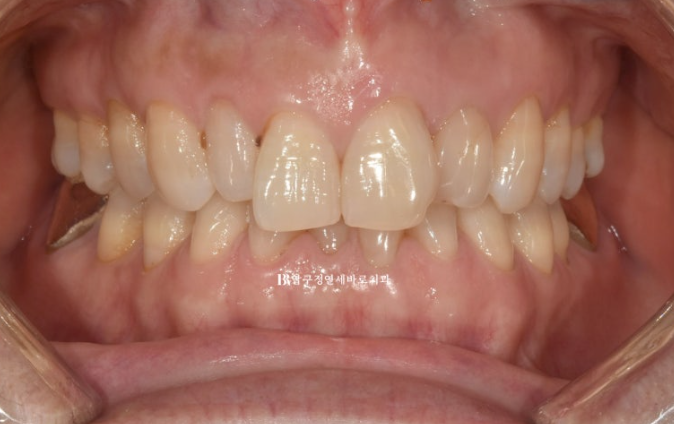

To match the patient’s desire for naturalness, the tooth shapes were designed to exclude artificial elements as much as possible.

Here is a comparison of the before-treatment and after-treatment photos, including Gelami.

23.09~24.08

Who would think this patient is in their 50s?

The teeth and smile look like they’re in their 20s, right?